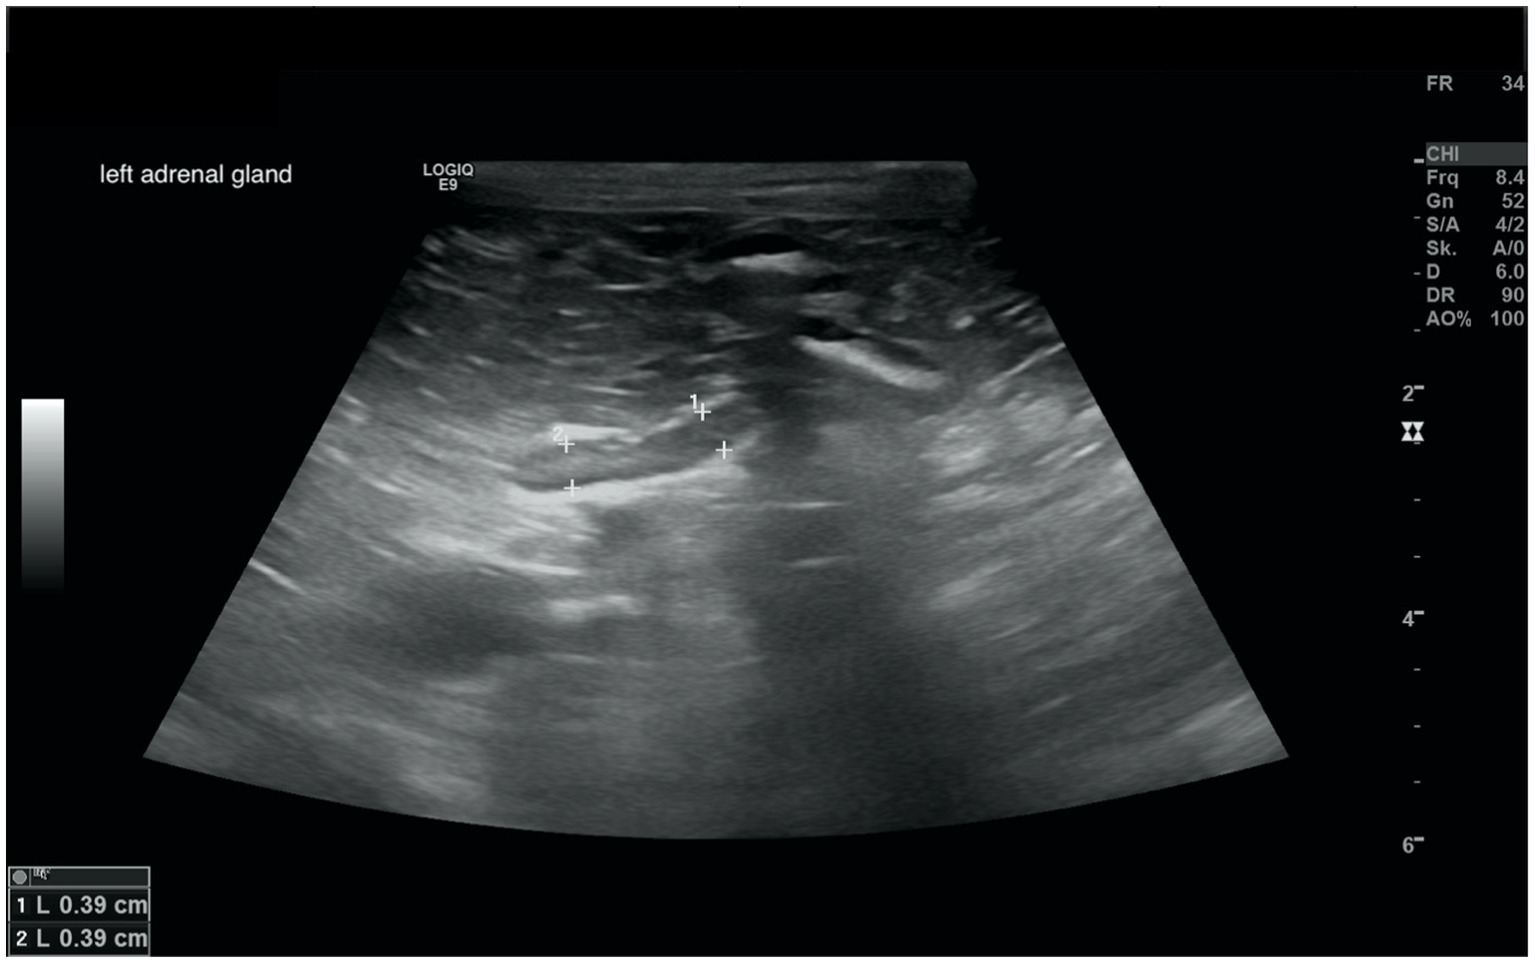

Figure 4

www.frontiersin.org

Figure 4. Ultrasound image of the smallest documented adrenal gland. This left adrenal gland measured 0.39 cm at the cranial and caudal pole, the right adrenal gland of this dog (not shown) measured 0.9 cm at cranial pole and 0.78 cm at the caudal pole; revaluation of the adrenals after 12 months revealed the following: cranial and caudal pole of the left adrenal gland 0.65 and 0.58 cm, cranial und caudal pole of the right adrenal gland 0.9 and 0.69 cm. Two years before the diagnosis of Cushing syndrome an ultrasound of the adrenal glands had been performed, revealing a left adrenal gland size of 0.48 cm and a right adrenal gland size of 0.53 cm.

In all dogs the maximum width of the adrenals was measured. The median maximum width of the left adrenal gland was 0.71 cm (IQR, 0.24 cm) and of the right adrenal gland was 0.75 cm (IQR, 0.19 cm). In a subset of dogs, measurements of the cranial and caudal adrenal poles were available. Thirty-eight measurements of the width of the cranial pole and 41 measurements of the width of the caudal pole of the left adrenal glands, and 38 measurements of the width of the cranial pole and 37 measurements of the caudal pole of the right adrenal glands were available. All detail data are shown in Table 6. The median difference between the two poles of the left adrenal gland (n = 37) was 0.11 cm (IQR, 0.12 cm) and of the right adrenal gland (n = 31) was 0.11 cm (IQR, 0.15 cm; Table 6). Figures 2, 3 show the measurement of a left and right adrenal gland. Figure 4 shows the image of the smallest documented adrenal gland.